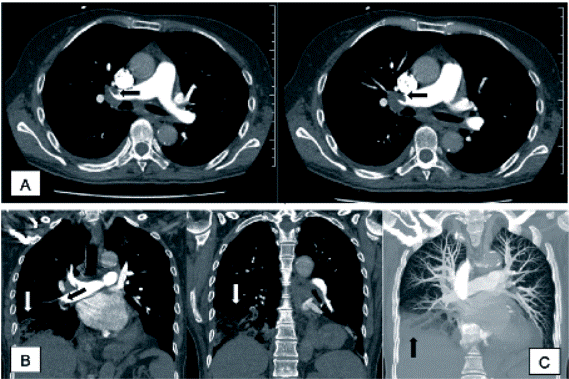

Se realizan paraclínicos de extensión sin evidencia de respuesta leucocitaria, sin anemia, ni irregularidades en el conteo plaquetario, destacando una importante cayademia (34 %) en el hemograma, con parámetros de función renal y electrolitos normales, gases arteriales en equilibrio de ácido base pero con hipoxemia (PO2 55 mm Hg). Los Rx de tórax de ingreso (figura 1) mostraban como hallazgos de relevancia una radio-opacidad a nivel basal derecha, por lo cual y teniendo en cuenta el cuadro clínico referido, hacen suponer un posible cuadro consolidativo de etiología infecciosa para el cual se inicia antibioticoterapia empírica.

Rx de tórax en proyecciones PA y lateral Nota explicativa de la imagen: se destaca la pérdida de ángulo costo-diafragmático derecho en relación con radio-opacidad que compromete el lóbulo inferior derecho, la cual igualmente genera pérdida de la radio-lucidez retrocardiaca.

Figura 1: Rx de tórax en proyecciones PA y lateral Nota explicativa de la imagen: se destaca la pérdida de ángulo costo-diafragmático derecho en relación con radio-opacidad que compromete el lóbulo inferior derecho, la cual igualmente genera pérdida de la radio-lucidez retrocardiaca.

Fuente: elaboración propia.